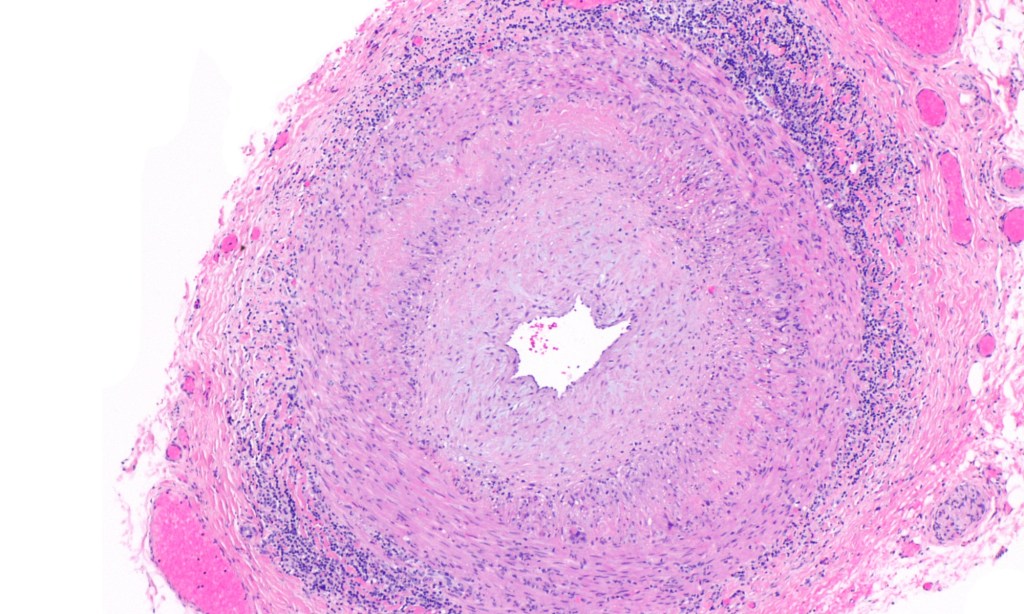

Ja, wirklich: Riesenzellarteriitis Heute geht es tatsächlich um die Riesenzellarteriitis, welche übrigens die häufigste Vaskulitis in den Industrieländern ist. Frauen sind doppelt so häufig wie Männer von einer Riesenzellarteriitis betroffen, die Prävalenz liegt bei 15-44/100.00, das typische Erstmanifestationsalter bei über 50 Jahren mit einer deutlichen Erkrankungshäufigkeitszunahme im höheren Lebensalter, insbesondere nach dem 80. Lebensjahr. Die…

-